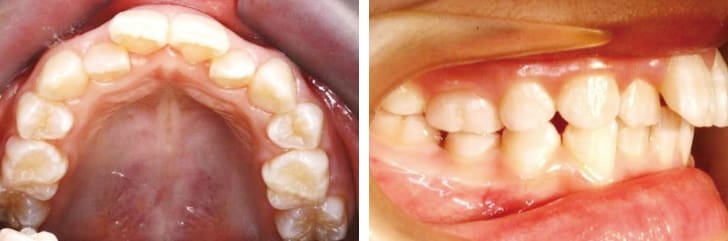

医師によってさまざまな考えがありますが、一般的にはまだ顎(あご)の発育が終わっていない8~9歳の間が良いと言われています。この時期であれば顎が発育中であるため、実際の矯正治療を始める前に、歯並びの改善に必要なスペースを作って、取り外し可能な装具を導入することも可能です。特に前歯が出てしまっているいわゆる“出っ歯”のお子さんの場合には、8~9歳ごろを目安に、早い段階から矯正を始めることをお勧めします。

出っ歯のお子さんは、ボールが当たる、壁にぶつかるなどの事故があった際に、前歯が折れてしまうケースも少なくないからです。こうした事故を未然に防ぐためにも、矯正治療は有効と言えるでしょう。

しかしながら、歯並びが複雑で入り組んでしまっている場合には、大人の歯に生え変わる10~11歳ごろの時期が理想的である場合もあります。

このころであれば、まだ歯の生え変わりも完了しておらず、インビザラインという透明マウスピースによる治療法を採用することで、更に矯正に伴う抜歯の必要性を最小限まで抑えることができます。15歳ごろになると歯の生え変わりも完了し、状況は変わってくるでしょう。